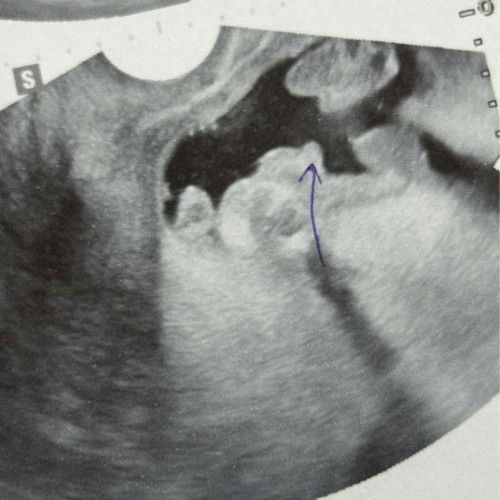

ทายเพศกันค่ะ

มีโอกาสย้ายทีมไหมคะ หมอบอกชาย100% แม่กลัวลูกย้ายทีมมากค่ะ🥹 17w